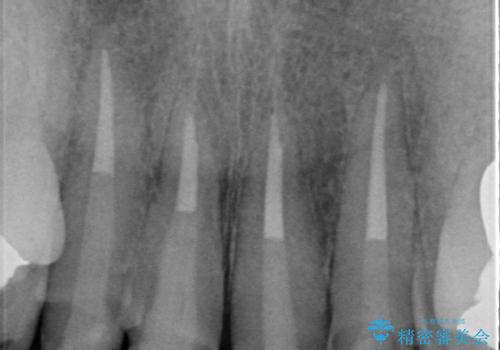

以前に治療した前歯クラウンは月日が経過することで劣化・歯肉の位置変化を引き起こし審美障害を引き起こしています。

劣化したクラウンを除去し、再発した虫歯を徹底的に除去したのち根管治療・ファイバーコア築盛を行いジルコニアクラウン製作へと移ります。

- 52万円(仮歯・ファイバーコア・ジルコニアクラウン×4)費用は治療当時の料金となります